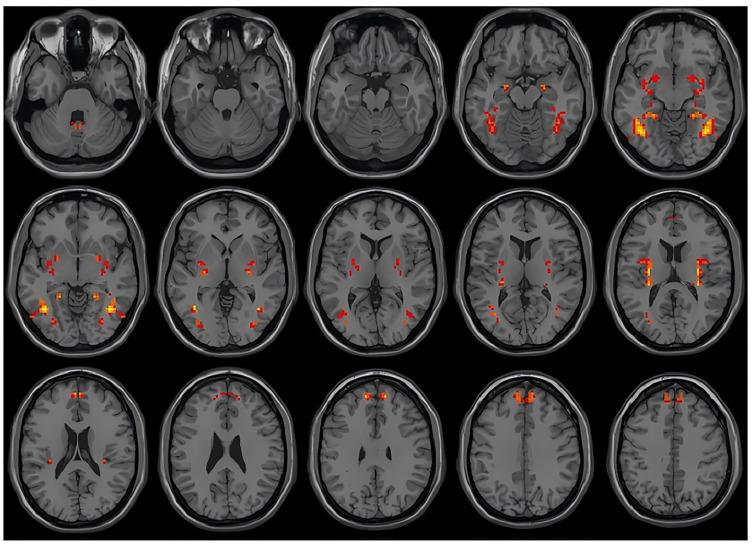

Patients with suicidal ideation exhibited significantly increased VMHC values in the superior frontal gyrus, putamen, inferior temporal gyrus, and cerebellum compared to those without suicidal ideation. The SVM model achieved an accuracy of 77.2%, sensitivity of 83.3%, specificity of 70.5%, and an area under the curve (AUC) of 0.81. When combining VMHC values from multiple brain regions, classification accuracy improved to 86.8%.

与无自杀观念的患者相比,有自杀观念的患者在额上回、壳核、颞下回和小脑中的VMHC值显著增加。SVM模型的准确率为77.2%,敏感性为83.3%,特异性为70.5%,曲线下面积(AUC)为0.81。当结合多个脑区的VMHC值时,分类准确率提高到86.8%。